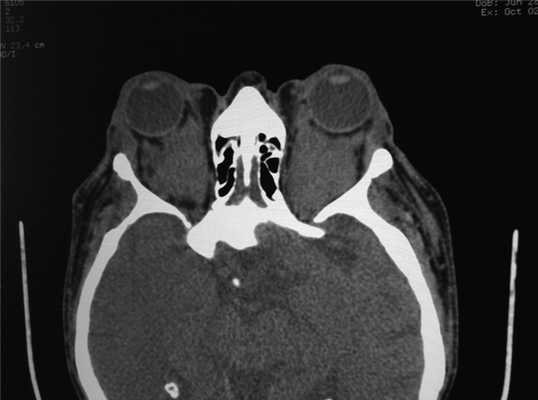

Ксантелазма обоих верхних век и двусторонний экзофтальм у мужчины 78 лет с системными признаками болезни Эрдгейма-Честера, в том числе с фиброзом легких и забрюшинной клетчатки. КТ, аксиальная проекция: пациент, представленный на рисунке выше; определяется очаговая инфильтрация мягких тканей глазницы. Ксантелазма верхнего века левого глаза у престарелой женщины с атипичной односторонней инфильтрацией, вызванной болезнью Эрдгейма-Честера. Двусторонний экзофтальм и атипичные ксантелазмы у пациента 28 лет. У пациента развилось тяжелое нарушение зрения обоих глаз, вызванное массивным поражением глазницы и сдавливанием зрительного нерва. КТ, аксиальная проекция: пациент, представленный на рисунке выше; определяется массивная инфильтрация обеих глазниц. КТ, корональная проекция, срез через среднюю часть глазницы пациента, представленного на рисунке выше; определяется протяженность поражения глазниц.

б) Диагностика. При лучевых исследованиях в глазнице выявляются диффузные мягкотканые образования, иногда заполняющие всю глазницу и вызывающие тяжелый экзофтальм (8). Хотя это заболевание часто поражает длинные кости, в глазнице патологический процесс обычно развивается в мягких тканях и значимое поражение кости отсутствует.

Рис. 3. Двусторонний экзофтальм. В ретробульбарной клетчатке орбит мягкотканые образования с неровными контурами полностью выполняющие полости глазниц.